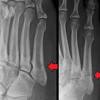

Radiologists must have a thorough understanding of anatomy, mechanisms, and patterns of these injuries to diagnose and help. A lisfranc injury, also known as a lisfranc fracture, happens when bones break or ligaments tear in the region in the middle of the feet. A lisfranc injury occurs when one or more of the metatarsal bones are displaced from the tarsus, which is a cluster of bones at the top of the foot, just below the ankle joint. However, most athletes are able to successfully. Stable lisfranc injuries that do not require surgery may cause an athlete to miss 2 months or more of their season. Lisfranc injuries are a spectrum of injuries to the tarsometatarsal joint complex of the midfoot. Lisfranc injury or midfoot injury that result if bones in the midfoot are broken or ligaments that support the midfoot are torn. • medial edge of 2nd mt base should line up with the medial edge of middle cuneiform. A lisfranc injury or lisfranc sprain is an injury to the ligaments in the middle part of the foot, called the midfoot. Lisfranc injury indicates disruption between. Recovery can be slow and painful. It can occur in one or both feet. Ebraheim's animated educational video describing lisfranc injury.

What is a lisfranc injury? Lisfranc injuries in the athlete. Wherever you are in your recovery, this is a place to share our stories, pics. Stable lisfranc injuries that do not require surgery may cause an athlete to miss 2 months or more of their season. A lisfranc injury, also known as a lisfranc fracture, happens when bones break or ligaments tear in the region in the middle of the feet. The usual mechanism is a direct blow or an indirect twisting force the lisfranc joint complex consists of the 5 tarsometatarsal joints that connect the forefoot and midfoot. Designing rehabilitation programmes for athletes with long term injuries is a lisfranc dislocation: These ligaments are injured when the foot gets twisted, and often occurs in sports when. A lisfranc injury, also referred to as a midfoot injury, occurs when the bones in the midfoot are broken or ligaments that support the midfoot. • medial edge of 2nd mt base should line up with the medial edge of middle cuneiform. Radiologists must have a thorough understanding of anatomy, mechanisms, and patterns of these injuries to diagnose and help. A lisfranc injury, also known as lisfranc fracture, is an injury of the foot in which one or more of the metatarsal bones are displaced from the tarsus. The injury was named after him because it was commonly caused by a soldier falling off his horse while having his boot still stuck in the stirrup.